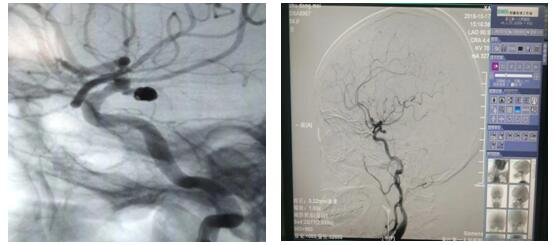

介入栓塞术是通过股动脉穿刺,将纤细的微导管放置于动脉瘤囊内或瘤颈部位,再经过微导管将柔软的钛合金弹簧圈送入动脉瘤囊内或瘤颈部位并将其填充,使得动脉瘤囊内血流消失,促进瘤内血栓形成,治愈动脉瘤。

近日,56岁的朱女士因“左侧面部麻木2天”入院,完善颅脑磁共振及头颈部CTA检查,示左侧颈内动脉与大脑中动脉交界处动脉瘤。DSA检查后,明确诊断“动脉瘤、动静脉畸形”瘤体大小为4-5mm,患者存在病灶侧动眼神经麻痹,考虑瘤体压迫所致,经苏大附二院肖国栋主任会诊后在全麻下行DSA脑动脉瘤栓塞术,整个手术过程顺利,全程用时1.5小时,患者麻醉苏醒后安返病房,经护理人员精心护理,目前患者病情平稳,在积极康复中。颅内动脉瘤介入栓塞术在我院是首次开展,手术的成功完成标志着我院神经内科脑血管介入治疗又登上了一个新台阶。同时,也填补了我院在这一领域的空白。